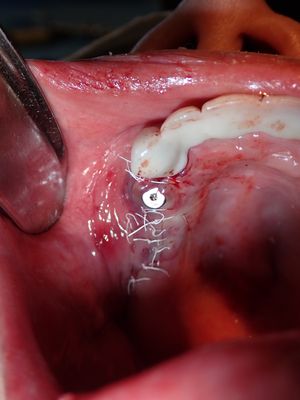

Mtiu - implant with bone expansion and graft

13 root is angled apex to the distal, 14 osteotomy positioned in region of thin bone, prepared to just under 2mm, remainder with densah drills, implant placed with bone around it countersunk. buccal region grated with sticky bone from 50/50 Mineralized cortical/cancellous followed by collagen membrane soaked in prf fluid, additional fibrin membrane overtop.